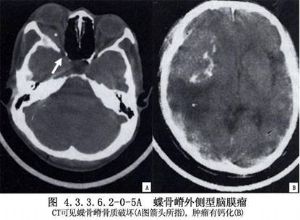

外侧型:肿瘤为球形、扁平形或二者之混合形。瘤体向外侧裂生长,并嵌入额叶的外侧与底面,颞叶的前部与底部。临床常引起癫痫、对侧轻度中枢性面瘫与肢体瘫痪。肿瘤压迫外侧裂附近的静脉,侧裂池脑脊液循环受阻,加上肿瘤占位,可由此引起颅内压增高。肿瘤在侧裂深部常与大脑中动脉干或主要分支粘连或包围动脉支。此部位肿瘤,尤其是扁平形者,经常伴有颅骨增生,蝶骨大翼骨质增生时,颞窝呈现骨性隆起,蝶骨嵴外侧骨质增生形成骨刺可伸入肿瘤基底。骨质增生范围可达眼眶顶部与后外侧壁,使该处骨质显著增厚,眼眶容积缩小,加之肿瘤向眼眶内生长,因此发生该侧眼球突出,并以一侧性、无痛性眼球突出为特点。肿瘤向内侧发展时,可累及眶上裂。

内侧型:起源于前床突与小翼内侧,肿瘤多为球形,毗邻为视神经、嗅神经、视交叉、眶上裂、颈内动脉的床突上段、分叉部、大脑中动脉和大脑前动脉的水平段、后交通动脉与海绵窦。有时肿瘤破坏眶上裂,向眼眶内生长,引起眼球突出和视力障碍。肿瘤向鞍上区及后上发展时,尚可引起垂体-下丘脑功能障碍。(图4.3.3.6.2-0-5A~C,4.3.3.6.2-0-6A~C)